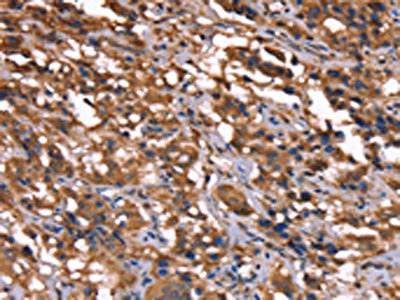

The image on the left is immunohistochemistry of paraffin-embedded Human thyroid cancer tissue using CSB-PA233008(GREB1 Antibody) at dilution 1/40, on the right is treated with synthetic peptide. (Original magnification: ×200)